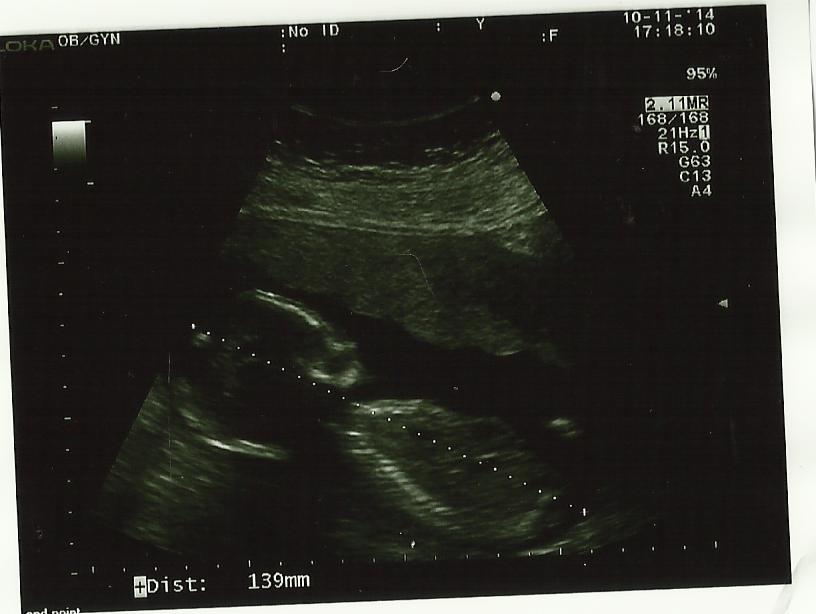

Op 10 november 2014 hadden mama en papa terug een afspraak bij dokter Lampaert.

Je bent ondertussen terug flink gegroeid. De gynaecologe vertelde dat je van het topje van jouw hoofdje tot het uiteinde van jouw poepje ondertussen 13.9 cm meet. Met de beentjes erbij ben je nu ongeveer 20 cm groot.

Je was trouwens zo schattig tijdens de echo. Je ligt precies met jouw armpjes te zwaaien naar mama en papa.